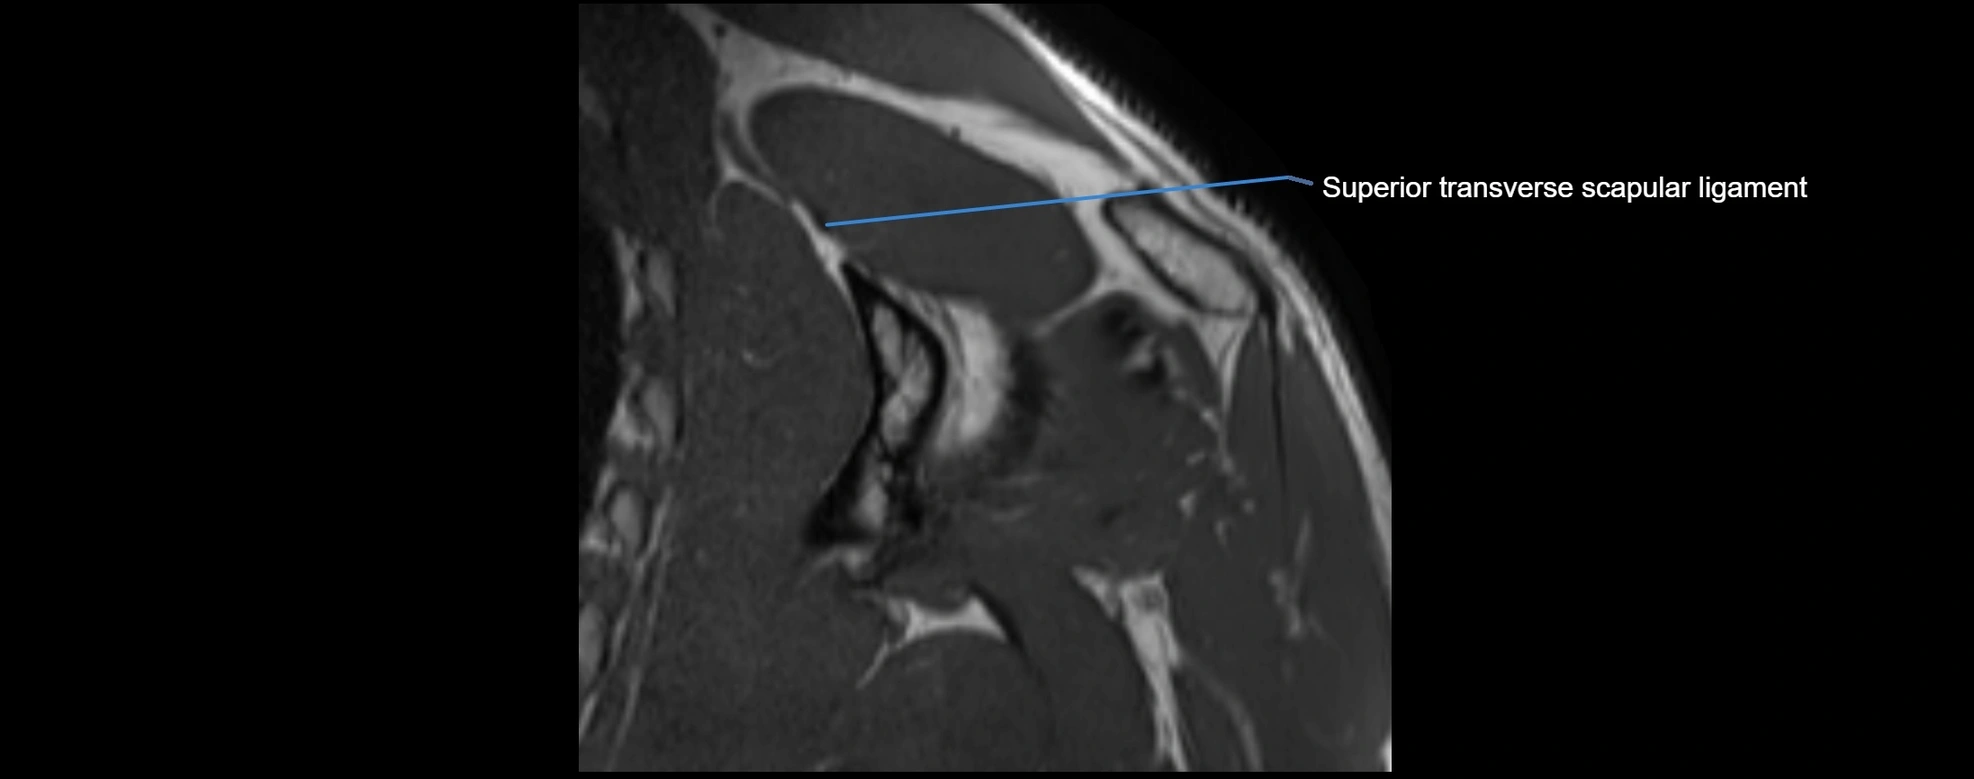

CT image

image